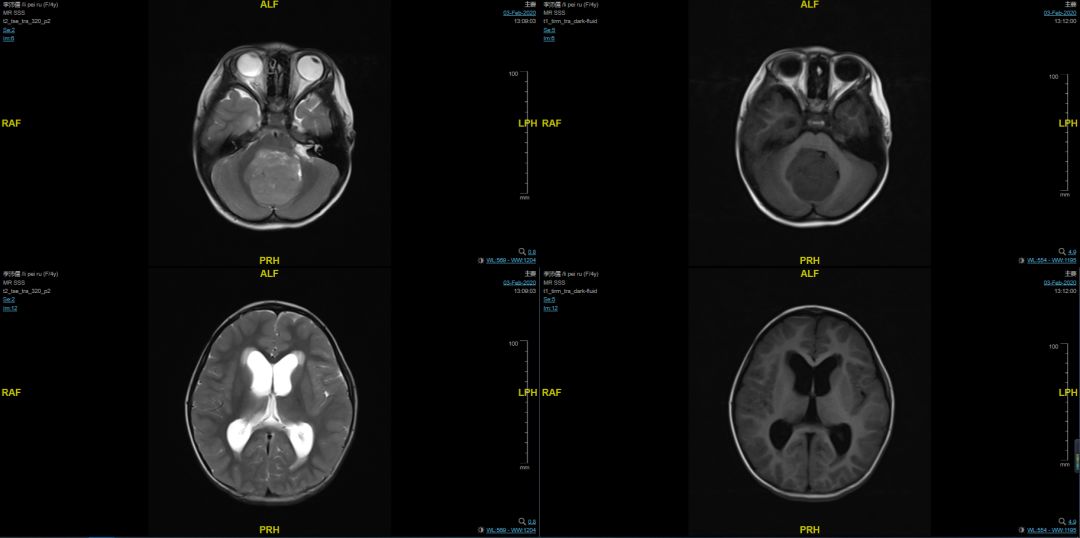

“急诊手术,女,4岁儿童,石家庄自驾。病人目前体温正常,但病情很差,嗜睡,恶心呕吐,走路不稳。当地医院的核磁共振成像显示后颅窝被占领和脑积水。当地没有动手术,病人在反复辗转反侧后,来到北京大学国际医院接受紧急治疗。”副局长叶迅的神经还没有完全放松,又绷紧了。虽然筋疲力尽,他坚定地回答:“我马上下来!”

看到病人,副局长叶迅吃了一惊。1例4岁女孩,后颅窝巨大占位并伴有严重脑积水,现已出现意识障碍,无需紧急手术即可随时发生呼吸和心脏骤停。

在完成胸部CT和血常规检查后,新的冠状肺炎被初步排除,但头部CT显示脑积水明显加重。刚刚完成手术的谭存信医生将很快准备好脑室穿刺和外引流设备,用于突发脑疝的紧急治疗。副主任叶迅详细制定了手术方案,并指导迅速完成术前检查和准备。

神经外科、呼吸与危重医学、传染病、麻醉、重症监护室等部门在消除疫情风险后,联合会诊并安排患者紧急手术。手术安排在核磁共振复合手术室。主任赵元利为主刀医师,副主任医师曾春、牛洪川、谭存信协助完成手术。术中核磁共振显示肿瘤完全切除,患儿术后恢复良好。核磁共振和CT复查显示脑积水没有恶化。现在,孩子已经顺利出院了。

患儿术前核磁共振儿童术前磁共振成像

患儿术后核磁及CT结果,提示占位切除,脑积水减轻

术后儿童的核磁共振和CT结果显示肿瘤被切除,脑积水得到缓解。